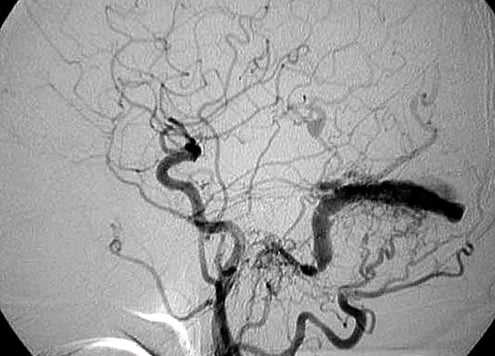

Бесконтрастная компьютерная томография (КТ) головного мозга эффективна только в диагностике неблагоприятных исходов ДАВФ — кровоизлияний и отека мозга, однако КТ-ангиография способна идентифицировать измененные артерии и вены, выраженную сосудистую сеть в дуральном синусе или мозговых оболочках, тромбоз венозного синуса. В ряде случаев аномальная перестройка сосудистой сети может быть скрыта артефактами, исходящими от костей черепа. Используя алгоритмы реконструкции для удаления костных структур на изображениях, недостатки исследования могут быть устранены [12, 21]. Однако «золотым стандартом» диагностики ДАВФ остается цифровая субтракционная ангиография [2, 10]. Благодаря высокому пространственному и временному разрешению катетерная ангиография позволяет получить информацию о расположении и анатомических особенностях соустья, идентифицировать важные особенности ДАВФ, такие как наличие кортикального рефлюкса, обструкции венозного оттока, аневризмы [9, 15, 19].

У одного из пациентов, наряду с наличием аневризмы супраклиноидного отдела левой внутренней сонной артерии, обнаружена сосудистая мальформация - дуральная артерио-венозная фистула в области задней черепной ямки с афферентацией в синусный сток (Рис. 1). В соответствии с тем, что происхождение аневризм и сосудистых мальформаций головного мозга, возможно, имеет одинаковую природу, наличие выявленной мальформации диктует необходимость поиска церебральных аневризм.

Большая часть (90%) всех диагностированных аневризм имела мешотчатую форму, остальные - фузиформную, а в одном наблюдении аневризма была смешанной (мешотчато-веретенообразная) формы и распологалась в месте бифуркации базилярной артерии (Рис. 2). По количеству камер все выявленные патологические образования являлись однокамерными. Определение формы аневризмы с помощью КТА имела большое значение для выбора дальнейшей тактики хирургического лечения. Так, аневризмы мешотчатой формы подвергались оперативному вмешательству с эндоваскулярным выключением аневризмы из кровотока.